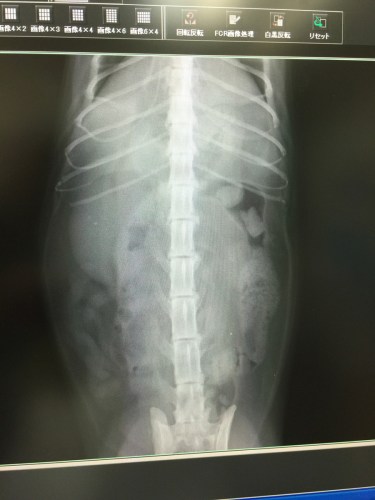

うおっほ、これがだいずさんのレントゲン写真です

いや全く無い訳ではありませんが3年前の写真と比べると明らかに左側が萎縮してます

その代わり動いている右側が肥大してフル稼働しているようです

だいずさんは生まれ付き左側の腎臓が機能不全と考えられます